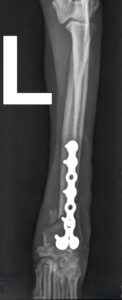

Bei der Nachoperation setzte Chirurg Maximilian Herion statt der gebrochenen Platte eine identische neue ein. Die Verwendung eines dickeren Implantats verbot sich wegen Hugos filigranem Knochen. Auch diesmal verlief die OP erfolgreich. So dass wir Hugo samt Herrchen mit guten Wünschen und einer erneuten Ermahnung, den Hund in einem Kinderlaufstall oder Käfig zu halten, nach Hause verabschieden konnten.